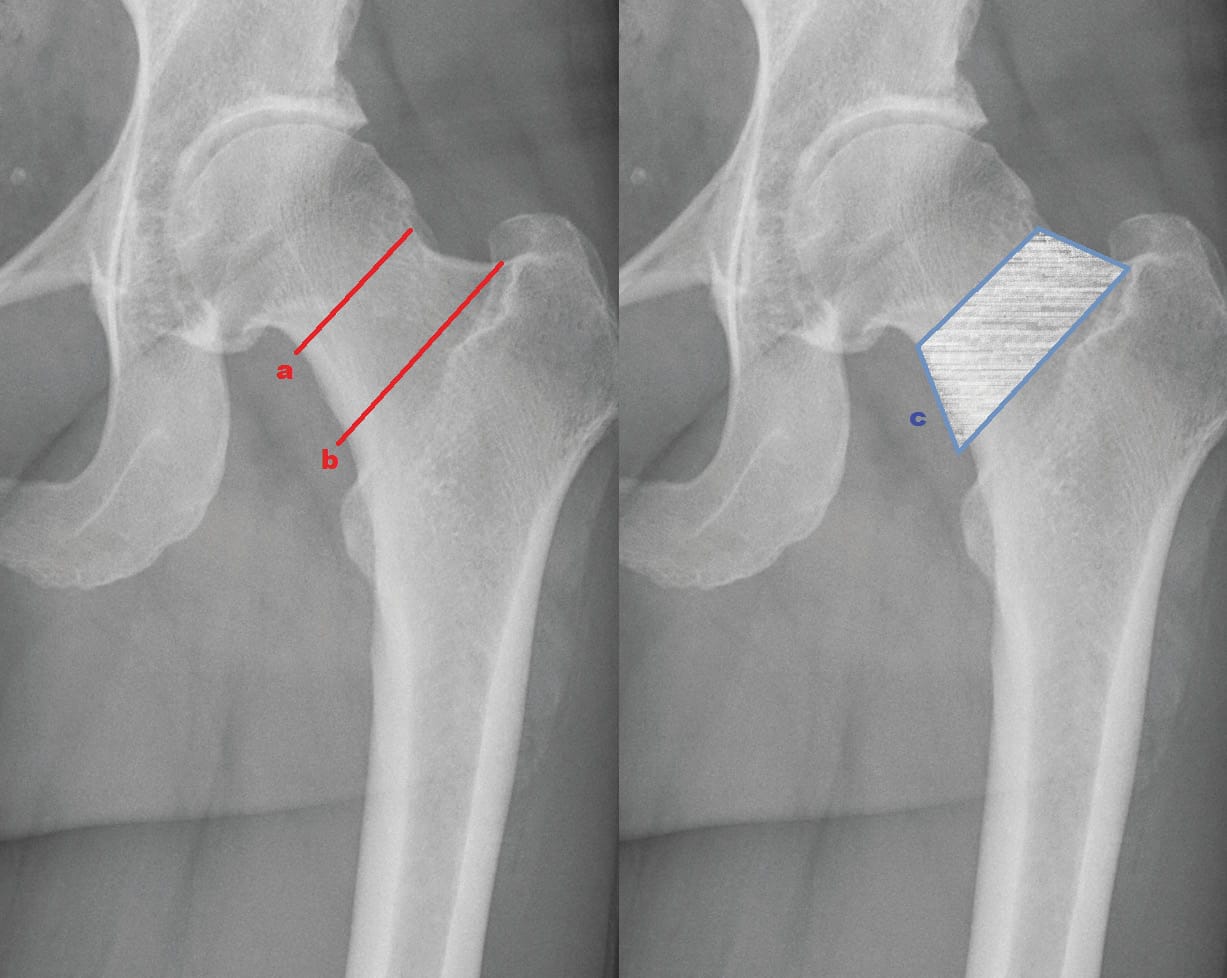

Neck retaining implants best allow sparing of bone (Figure 2a). However, also a

superior quality of bone for this kind of implants is essential. The reconstruction of individual anatomy and biomechanics is very limited. Due to high revision rates, these stems did not prove to be reliable and mostly have been withdrawn from the marked (Cut, ESKA Implants; Silent, Depuy-Synthes) [9] Nieuwenhuijse MJ, Valstar ER, Nelissen RGHH (2012) 5-year clinical and radiostereometric analysis (RSA) follow-up of 39 CUT femoral neck total hip prostheses in young osteoarthritis patients. Acta Orthop 83:334–41. doi: 10.3109/17453674.2012.702392..

Neck resecting short stems largely correspond to the philosophy of past conventional straight stems and require similar quality of bone (Figure 2b). In order to reconstruct hip geometry in terms of offset and leg length, a high amount of modularity and different sizes is needed and often accuracy is poor [10] Höhle P, Schröder SM, Pfeil J (2015) Comparison between preoperative digital planning and postoperative outcomes in 197 hip endoprosthesis cases using short stem prostheses. Clin Biomech 30:46–52. doi: 10.1016/j.clinbiomech.2014.11.005..

The third group in the classification by Jerosch consists of the partially neck retaining short stems (Figure 2c). Almost all new-generation short-stem designs derive from this group. They enable a great variability using a special calcar-guided implantation technique. An individualized level of resection of the femoral neck plays the most important role [13], Kutzner KP, Donner S, Schneider M, et al. (2017) One-stage bilateral implantation of a calcar-guided short-stem in total hip arthroplasty. Oper Orthop Traumatol. doi: 10.1007/s00064-016-0481-5.[14] Kutzner KP, Pfeil J (2018) Individualized Stem-positioning in Calcar-guided Short-stem Total Hip Arthroplasty. J Vis Exp. doi: 10.3791/56905. The level of resection is individually chosen according to the preoperative planning in order to reconstruct offset and leg length [15] Kutzner KP, Kovacevic MP, Roeder C, et al. (2014) Reconstruction of femoro-acetabular offsets using a short-stem. Int Orthop. doi: 10.1007/s00264-014-2632-3.. The positioning of the implants thus can be varied [16] Kutzner KP, Freitag T, Donner S, et al. (2017) Outcome of extensive varus and valgus stem alignment in short-stem THA: clinical and radiological analysis using EBRA-FCA. Arch Orthop Trauma Surg 137:431–439. doi: 10.1007/s00402-017-2640-z.. Early representatives of these partially neck retaining implants are the Pipino-stem (Link) and the C.F.P. (Link). The newest generation of modern short stems consists exclusively of calcar-guided short stems, such as the Nanos-stem (Smith&Nephew), the Minihip-stem (Corin) and the optimys-stem (Mathys Ltd Bettlach) (Figure 3).